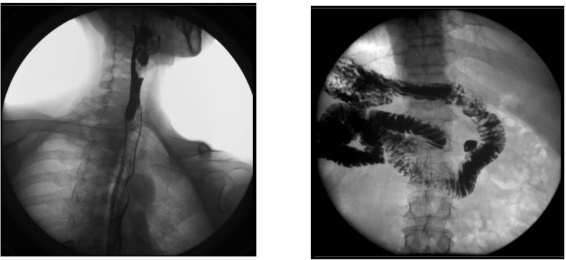

2、數(shù)字化胃腸功能:適用于胃腸道造影檢查,如食管造影、上消化道造影、全消化道造影等。

1) 消化內(nèi)科:可檢查直腸炎、結(jié)腸炎等;

臨床表現(xiàn)為腹痛、便秘等,癥狀為便血、黑便等。

2) 肛腸科:可應(yīng)用氣鋇雙重造影和排便造影(DFG)功能,可檢查大腸的細(xì)小病變,如小息肉、早期腫瘤、潰瘍等效果良好;可檢查肛管炎、恥骨直腸肌綜合癥、骶骨部畸胎瘤、直腸前突、直腸內(nèi)套疊、肛門直腸損傷和異物等檢查。

3、其他造影:適用于各種普通及特殊造影,如口服膽囊造影、靜脈膽道造影、T 管造影、逆行胰膽管造影(ERCP)、靜脈腎盂造影(IVP)、子宮輸卵管造影等。

1) 婦科:可檢查輸卵管堵塞、輸卵管粘連、輸卵管積水等慢性輸卵管疾病導(dǎo)致的不孕,可明確顯示輸卵管堵塞的部位、程度及性質(zhì),還可辨認(rèn)子宮內(nèi)膜情況,輸卵管和盆腔的結(jié)核病變情況;

2) 肝膽外科:膽管手術(shù)后,切開膽總管植入 T 管引流,起支撐作用,防止術(shù)后膽總管狹窄,術(shù)后應(yīng)用胃腸機(jī)進(jìn)行膽管造影(T 管造影),檢查膽道內(nèi)有無(wú)殘留結(jié)石及異物,是否通暢無(wú)阻, 對(duì)手術(shù)進(jìn)行評(píng)估;